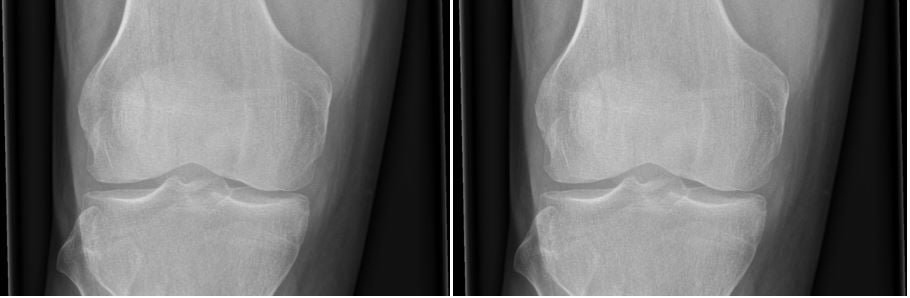

This is a normal knee X-ray as would be expected with PFS

Case courtesy of Dr Andrew Dixon, Radiopaedia.org. From the case rID: 36689